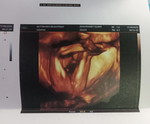

33Week

33วีคเท่ากันเลยค่ะน้องน้ำหนักเท่าไหร่คะแม่

ดีจังนี่แค่1688เองค่ะ